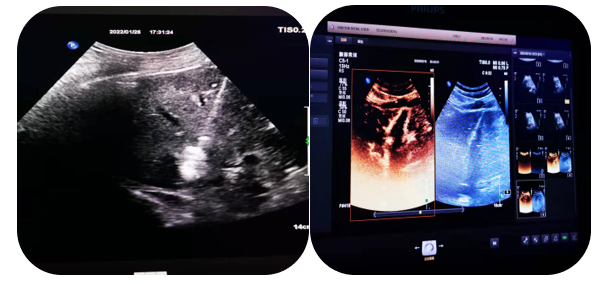

1.超声引导下穿刺活检

超声的实时引导下,穿刺针插入肿大淋巴结、疑似占位等特定部位进行组织抽吸、切割获取病理标本帮助疾病诊断。

超声引导下浅表淋巴结穿刺活检